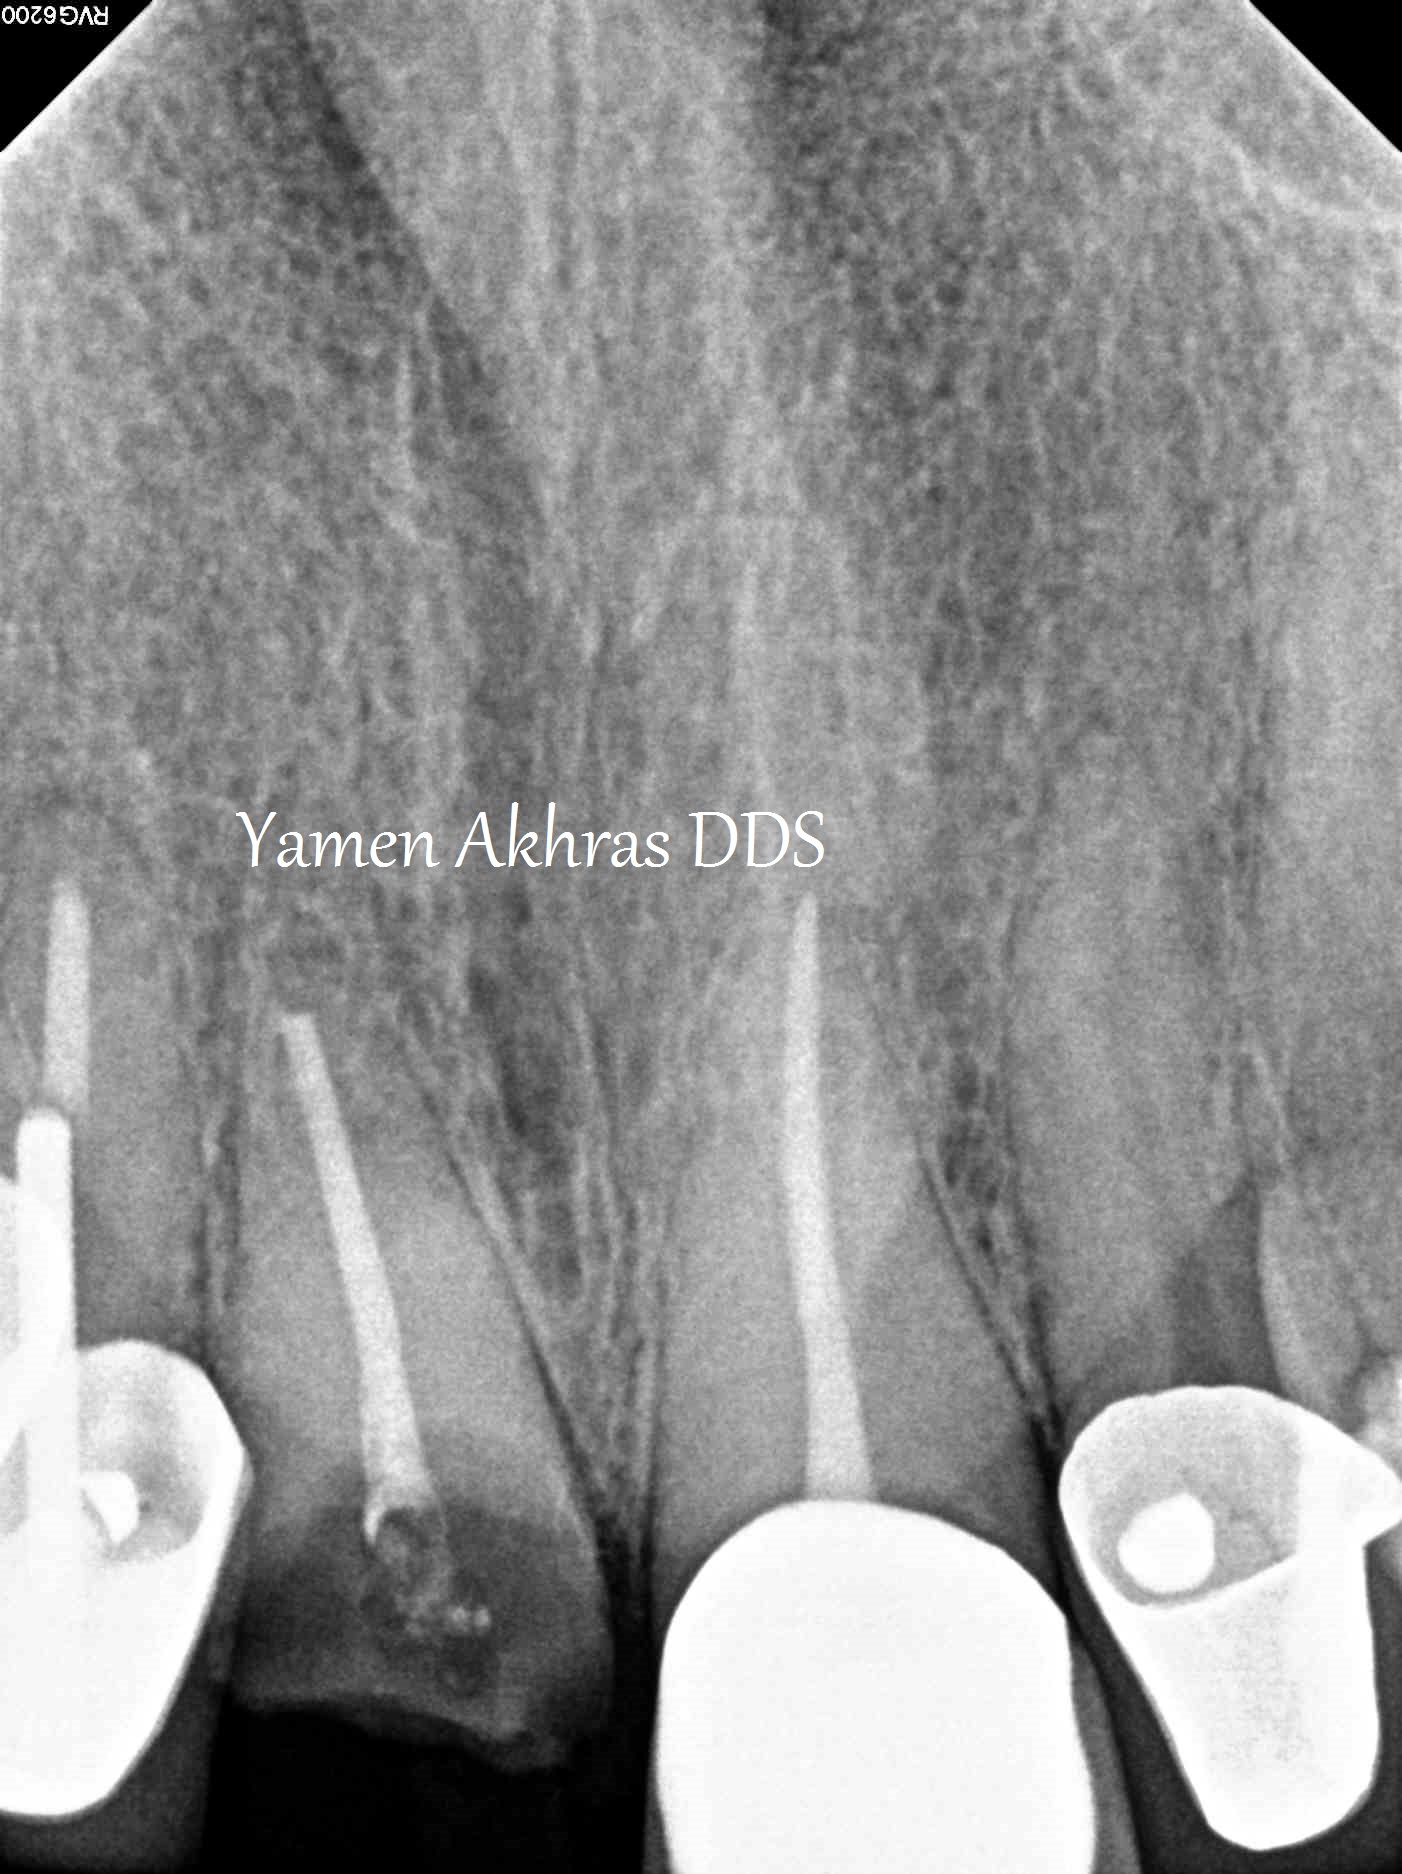

Front tooth restored with dental implant

Our patient had fractured a front tooth in an accident and needed a quick and permanent fix for her front tooth. The tooth was extracted and an immediate implant was placed the same day. After 4 months of healing we achieved an excellent emergence profile and a custom titanium abutment was torqued in. A permanent porcelain fused to metal dental crown was placed in the #8 area (to match her other crowns). We attached photos for this case. During treatment planning a CBCT scan was done of the upper arch to diagnose the qaulity and the quantity of the bone in this area. Dr. Yamen Akhras places dental implants at his office, where general dentistry and orthodontics are also services that are offered. Call today for a consultation with the doctor.